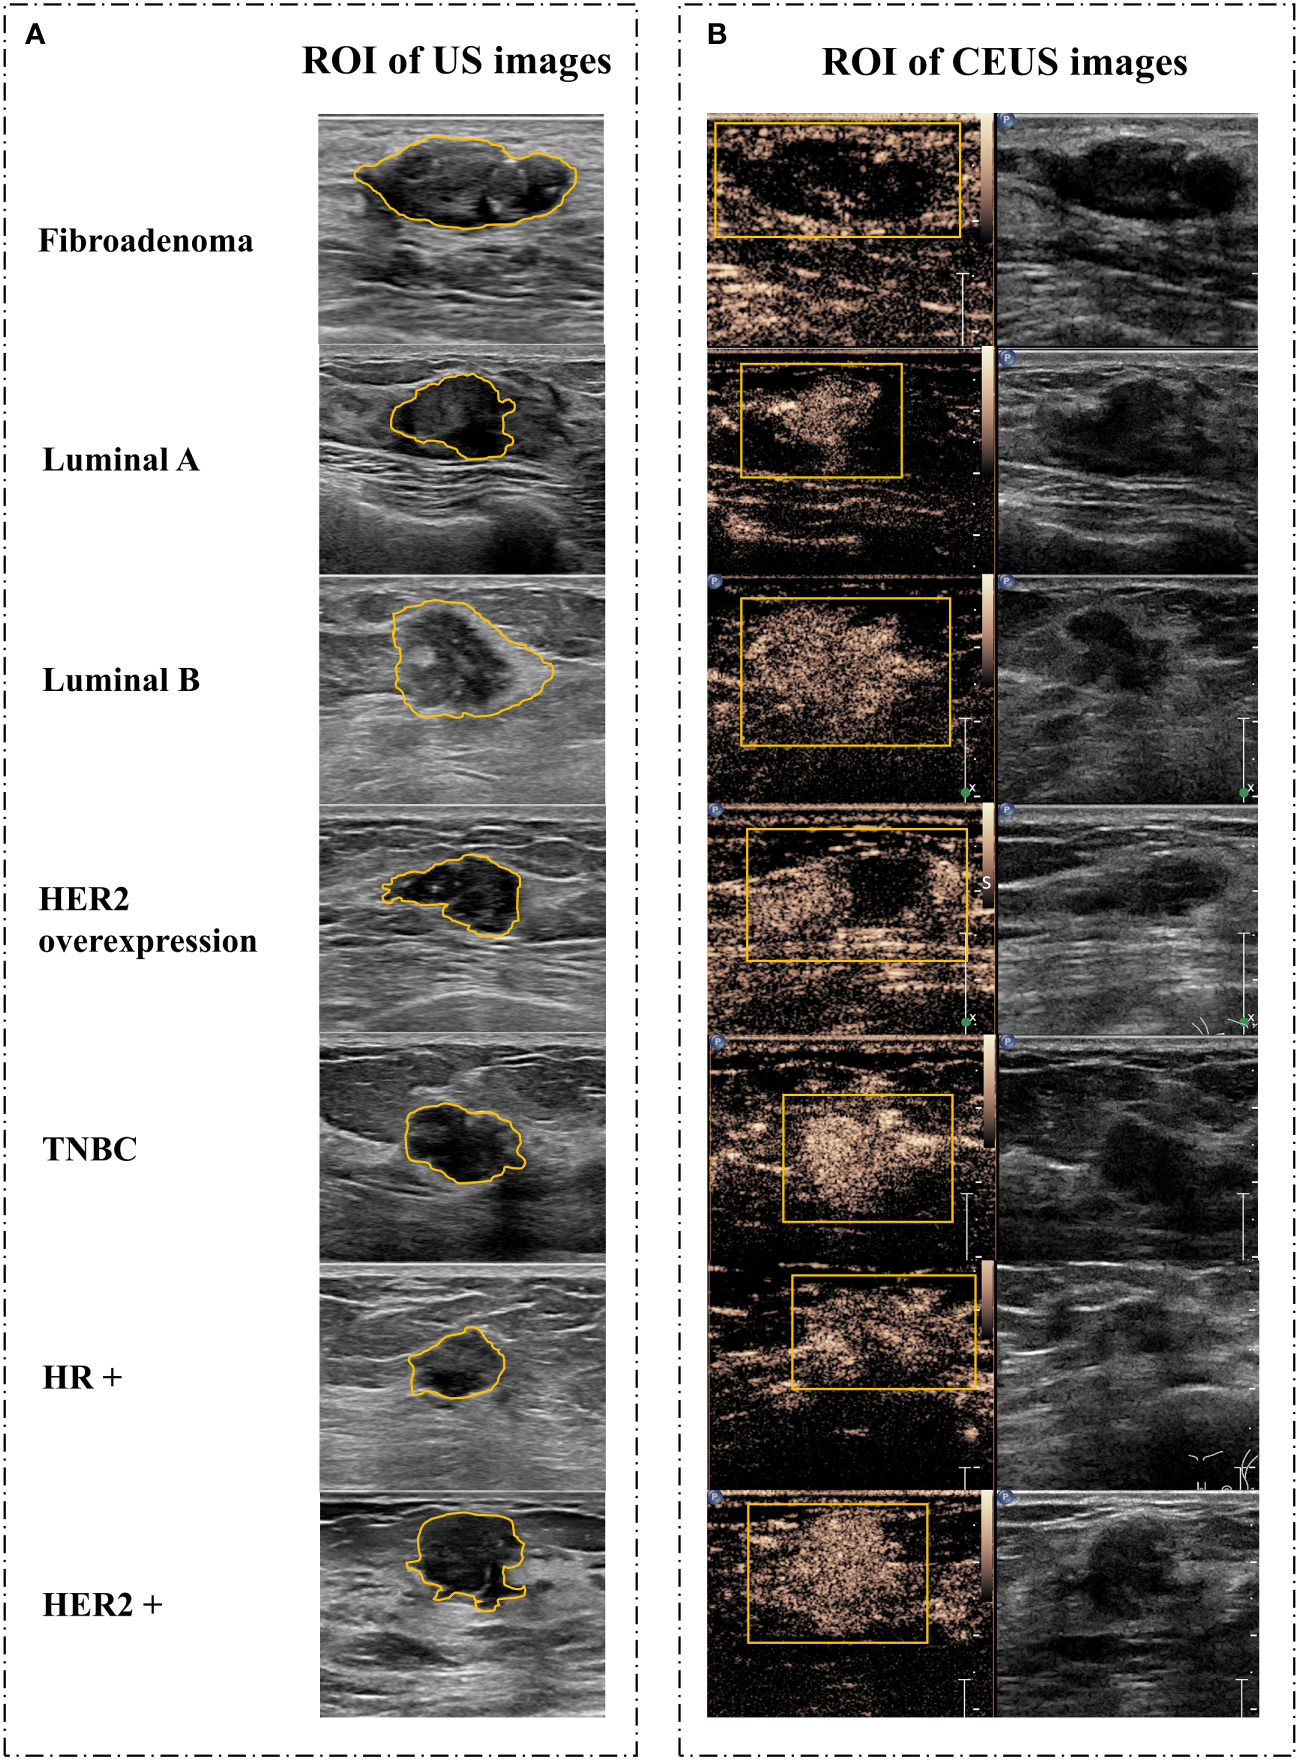

There were 967 images of CUS, and 170 videos of CEUS in total. The region of interest (ROI) sketch was drawn manually by two senior physicians and areas with disagreement were jointly assessed. The ROI of CUS images was outlined around the tumor, including the hyperechoic halo. For the ROI of CEUS videos, it was first outlined with a rectangular box in the frame that the tumor displayed clearly (Figure 2), and then, a computer vision algorithm was used to track and draw all the ROI sketches across all the frames in the video (20).

Figure 2

Image segmentation. (A) Schematic diagram of CUS images. (B) Schematic diagram of corresponding CEUS images with the peak intensity. CUS, conventional ultrasound; CEUS, contrast-enhanced ultrasound; ROI, region of interest; HER2, human epidermal growth factor receptor 2; TNBC, triple-negative breast cancer; HR, hormone receptor.